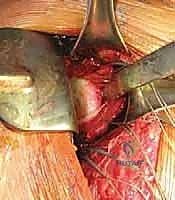

الخطوة 1: التقييم بالمنظار (Diagnostic Arthroscopy)

بعد تخدير المريض، يقوم البروفيسور هطيف بعمل 2 إلى 3 شقوق صغيرة جداً (لا تتجاوز نصف سنتيمتر) حول الكتف. يتم إدخال كاميرا دقيقة (المنظار) وأدوات جراحية متخصصة. تتيح الكاميرا رؤية المفصل من الداخل بوضوح فائق لتقييم حجم التمزق في الشفا الحقاني (آفة بانكارت) ودرجة ترهل المحفظة.

الخطوة 2: تحضير العظم والأنسجة (Tissue Preparation)

يتم تنظيف الحافة الأمامية للتجويف الحقاني وإزالة الأنسجة المتليفة باستخدام أدوات دقيقة. هذه الخطوة حاسمة لتحفيز تدفق الدم وخلق سطح عظمي خشن يسمح للأنسجة الممزقة بالالتئام والاندماج مع العظم بقوة لاحقاً.